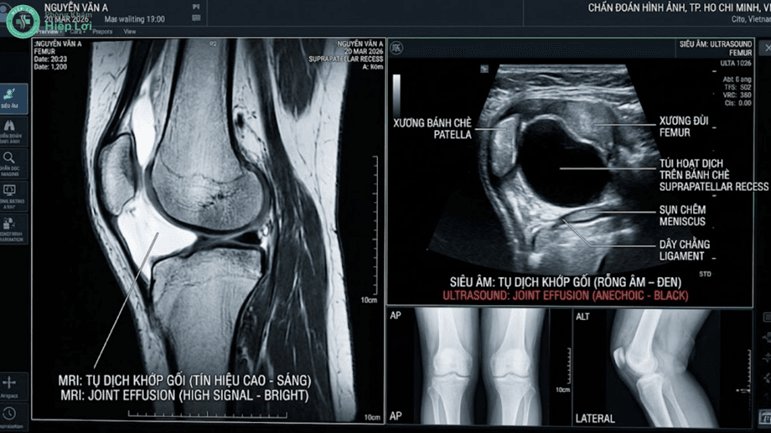

- Siêu âm khớp gối: Đánh giá độ dày màng hoạt dịch và đo lường thể tích lượng dịch đang ứ đọng.

- Chụp X-quang/MRI: Tầm soát các nguyên nhân cốt lõi như gai xương thoái hóa, rách sụn chêm hay đứt dây chằng chéo.

Siêu âm và chọc hút dịch khớp là những kỹ thuật bắt buộc để bác sĩ chẩn đoán nguyên nhân và quyết định phác đồ dùng thuốc.